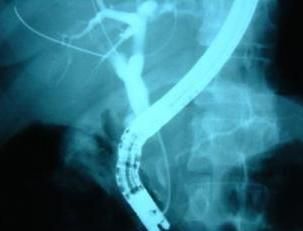

Figure 1.

Endoscopic retrograde cholangiogram (ERCP) revealed a CBD obstruction with upstream biliary dilation, suggestive of an impacted gallstone (Figure 1). Sphincterotomy was performed and a biliary stent was placed for decompression. Analysis of the collected bile revealed parasitic organisms (multiple ova [Opisthorchis felineus]) (Figure 2), and a ventral sucker of an adult liver fluke (Figure 3).